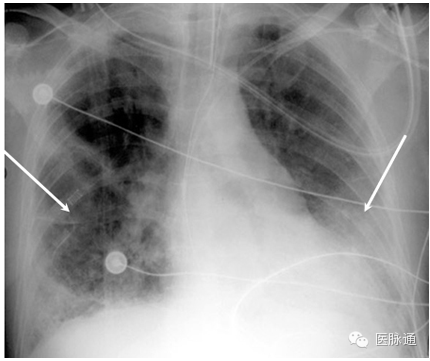

充血性心力衰竭是指心脏泵出的血不能满足组织代谢需要的临床综合征。胸片可出现多种典型的表现。心脏增大,后前位胸片显示心胸比例增加超过50%(图11白线)。小叶间隔增厚导致肺组织周边可能出现Kerley B线。胸膜液积聚可使肋膈角变钝(红色箭头)或导致大量胸腔积液。肺水肿可以引起双侧肺纹理增加,或呈蝙蝠翅状分布。肺毛细血管压增加导致上叶血管直径与下叶血管直径相当或更粗,即头侧化。

图11